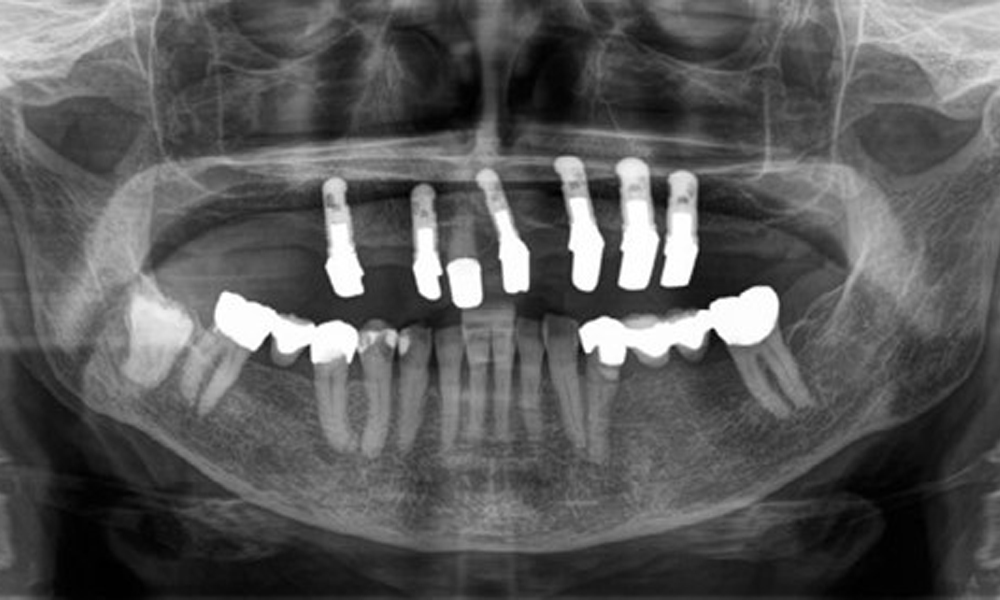

Die Patientin wurde vor über 25 Jahren mit einer kombinierten herausnehmbare Implantat-Teleskopprothese im Oberkiefer versorgt (Abb. 1, Abb. 2, Abb. 3) und ist sehr glücklich über ihren Zahnersatz. Im Unterkiefer hat die Patientin einen suffizienten festsitzenden Zahnersatz. (Abb. 4)

Der dentale Befund stellt sich wie folgt dar: Kombinierte herausnehmbare Implantat- und zahngetragene Teleskoparbeit auf Implantaten 15, 13, 21, 23, 24, 25 und Zahn 11 (Abb. 1, Abb. 2, Abb. 3). Im Unterkiefer ist die Patientin mit einem festsitzenden Zahnersatz versorgt. 37–34 sowie 45–47 haben suffiziente Brücken (Abb. 4). Kronenränder sind intakt, aktive kariöse Läsionen sind nicht vorhanden. An Zahn 43 zeigt sich eine Compositefüllung mit Randspalt. Im Unterkiefer liegen Rezessionen mit freiliegender Wurzeloberfläche zwischen 1 – 3 mm vor. Dies trifft auch für 11 zu.